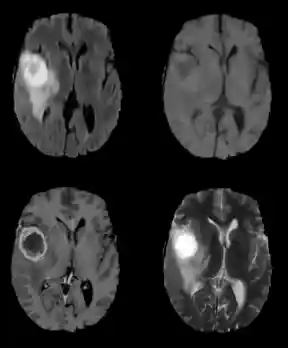

There are multiple radio frequency pulse sequences that can be used to illuminate different types of tissue. For adequate segmentation there are often four different unique sequences acquired: Fluid Attenuated Inversion Recovery (FLAIR), T1, T1-contrasted, and T2 (Figure 4). Each of these pulse sequences exploits the distinct chemical and physiological characteristics of various tissue types, resulting in contrast between the individual classes. Notice the variability in intensities among the four images in Figure 4, all of which are images of the same brain taken with different pulse sequences.

Figure 4: Flair (top left), T1, T1C and T2 (bottom right) pulse sequences.Segmentation